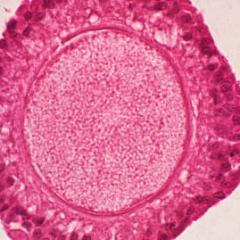

Oocyte

Oocyte Zygote